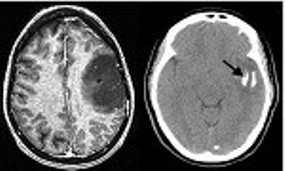

Oligodentroglioma

La generación de nuevos vasos sanguíneos de los gliomas es uno de los elementos del microambiente tumoral más importantes en la progresión y agresividad de los gliomas. A veces, las células tumorales se incorporan a la estructura de los vasos sanguíneos, reforzando así las vascularizaciones de tumor y favoreciendo su crecimiento.

Bajo la dirección de Pilar Sánchez y Ricardo Gargini, la investigadora Berta Segura-Collar, primera firmante del estudio, y su equipo han estudiado el proceso molecular de esta generación de nuevos vasos sanguíneos y lo han relacionado con la genética de los gliomas. El 90 % de los tumores tienen mutaciones en el gen IDH y/o en el gen EGFR. Los investigadores, en un estudio previo, habían demostrado que las mutaciones en IDH impiden la generación de nuevos vasos sanguíneos. Ahora se demuestra que los gliomas que tenían alteraciones en el gen EGFR, los de rápida progresión, aumentan su crecimiento por la capacidad de las células cancerosas para fabricar vasos sanguíneos.